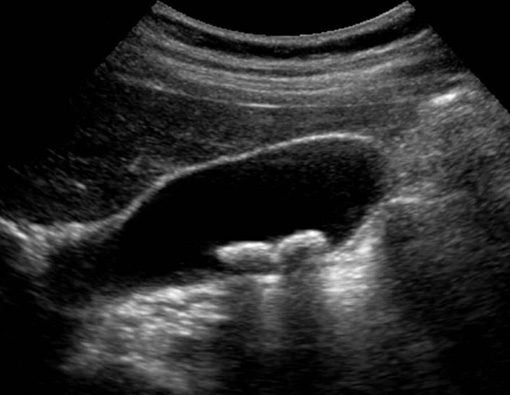

Below are images of the urinary bladder and kidney via ultrasound.

URINARY BLADDER WITH STONES

At Urban Vet we routinely use the Ultrasound for guided urine collection. This allows us to obtain a sterile sample as well as examine the bladder wall and visualize masses or stones within the bladder simultaneously. This is the safest, most effective way to collect urine in our pets.